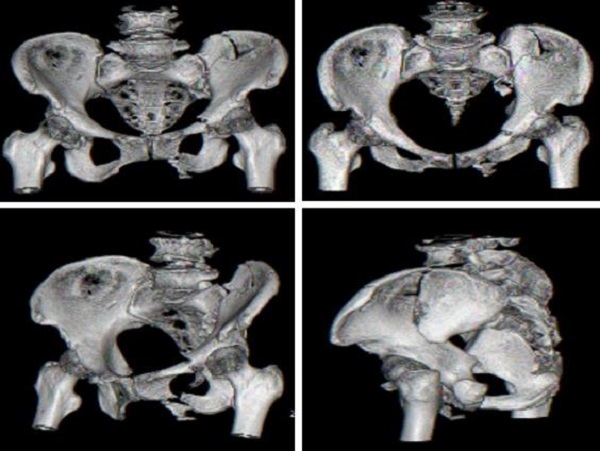

术前CT检查: